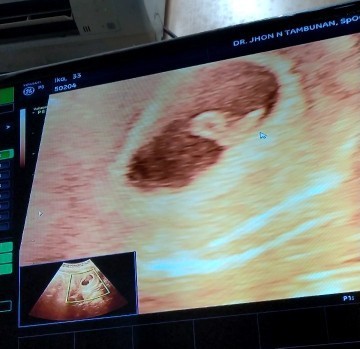

4 minggu bund